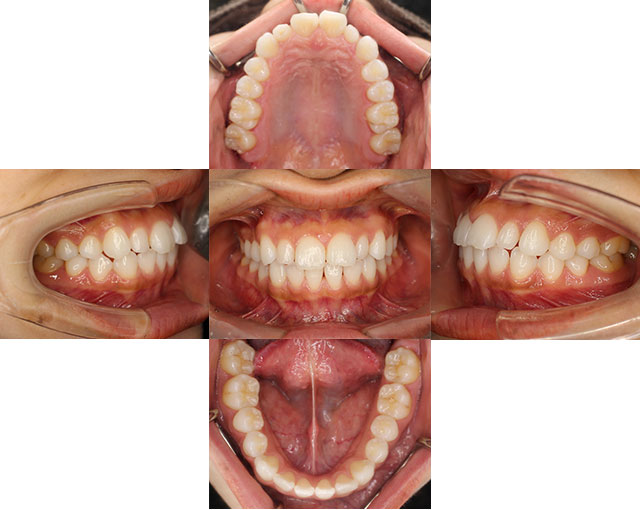

口腔内写真

歯の形態や歯列、かみ合わせの状態の確認をします。

治療経過の記録や、治療前後の比較、患者様への説明に使用するためにも使います。